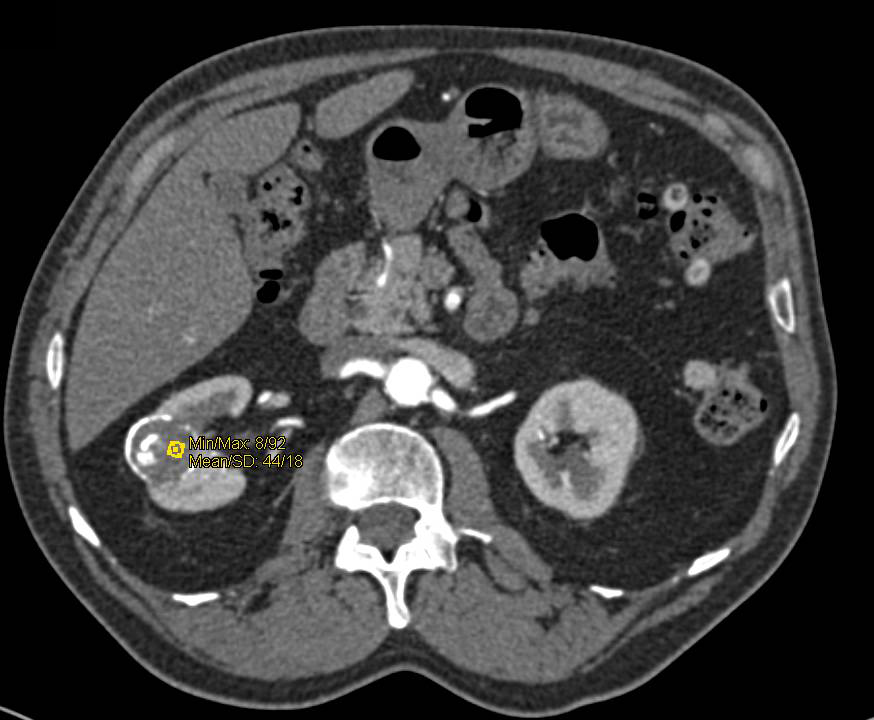

КТ ретроперитонеального фиброза: Изображения и диагностика

Раздел: Мудрость в деталях